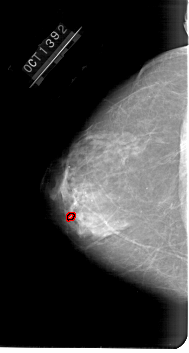

A_1647_1.RIGHT_MLO

RIGHT_CC LINES 6211 PIXELS_PER_LINE 3031 BITS_PER_PIXEL 12 RESOLUTION 43.5 NON_OVERLAY

FILE: A_1647_1.LEFT_MLO.OVERLAY

TOTAL_ABNORMALITIES 1

ABNORMALITY 1

LESION_TYPE CALCIFICATION TYPE PLEOMORPHIC DISTRIBUTION CLUSTERED

ASSESSMENT 4

SUBTLETY 1

PATHOLOGY BENIGN

TOTAL_OUTLINES 1

BOUNDARY